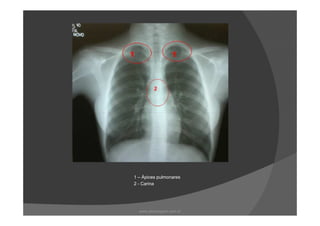

1 – Ápices pulmonares

2 - Carina

1 – Ápicespulmonares 2 - Carina www.playmagem.com.br